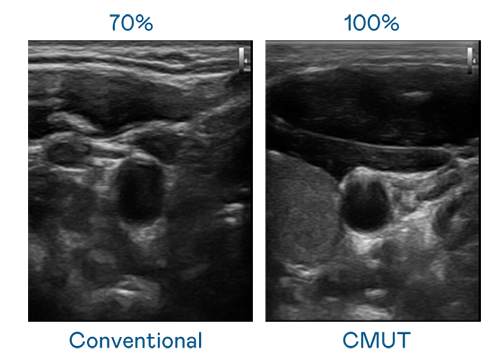

CMUT 技术是一种用电容式微机电元件来产生超音波讯号的技术。与传统 PZT 压电式技术相比,CMUT 频宽增加 30%,更宽频的超音波讯号让影像解析度大幅提升,是实现高影像品质医疗超音波扫描、促进精准医疗发展的关键技术。

大频宽带来超清晰影像

超音波影像的解析度高低,首先取决于探头能发出的讯号频宽。麻花豆国产剧视 CMUT 可提供高清晰的超音波讯号,提供高频宽、高灵敏度、影像纹理细节更高的超音波影像,协助医护人员缩短影像判读时间及利用精准的医疗影像进行诊断。